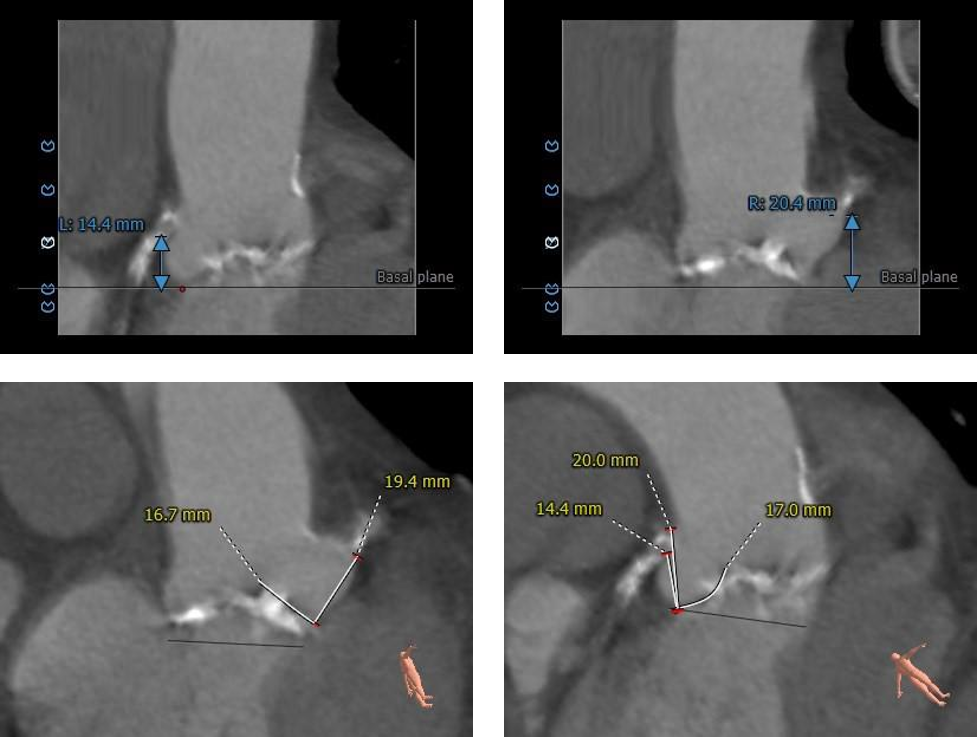

术前CT评估:

主动脉根部评估:

三叶式主动脉瓣,LVOT收口型,横位心。

冠脉评估:

冠脉开口高度可,左冠瓣叶长于开口下缘到附着点距离。

钙化评估:

重度钙化,集中分布于左冠窦、右冠窦内。

入路评估:

外周血管内径可,走形适宜;主动脉弓宽度、夹角可。

CT评估分析